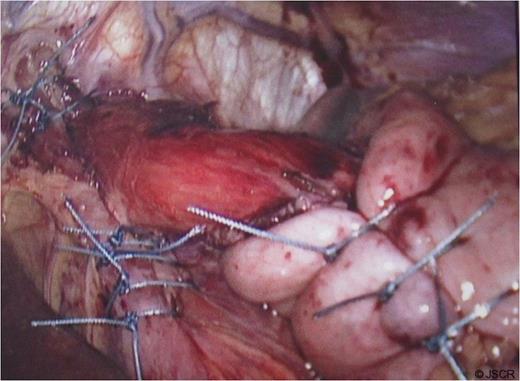

Chest pain persisted and the patient required higher pressure CPAP to maintain adequate oxygenation. Auscultation consistently showed decreased air-entry in the lung bases. On day 3, a repeat chest x-ray showed a left lower lobe collapse above the gastric bubble in the mid zone of the chest (Fig. 4 & 5). CTPA done on the same day to exclude pulmonary embolism confirmed a para-oesophageal hernia that was pushing against the left lung base. Ultrasound scan of the left chest also showed movement of the diaphragm below the gastric bubble.

Chest x-ray on 3rd post-op day showing prominent left sided collapse/ consolidation

Post-op CT-scan demonstrating the left sided pleural effusion with collapse /consolidation & patchy opacification on the right side.